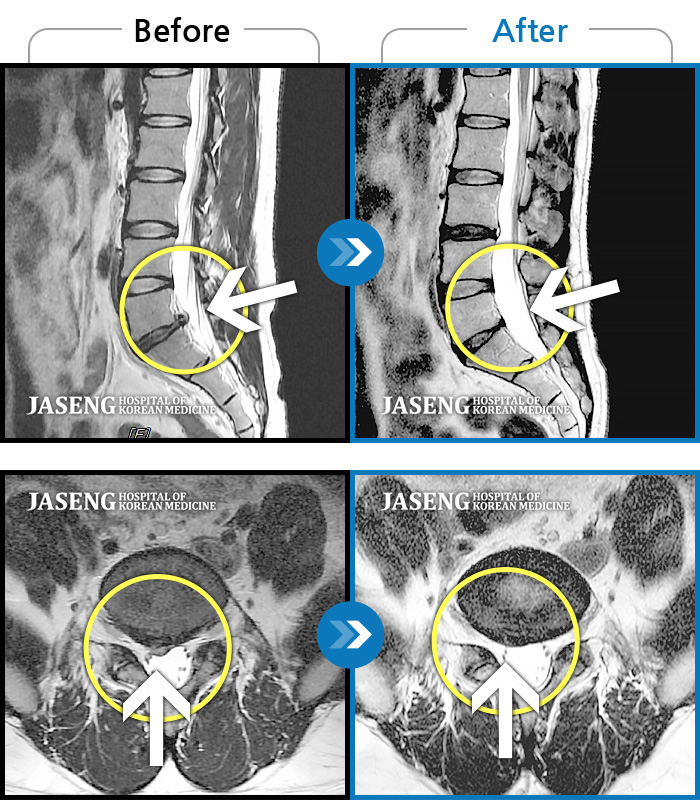

허리디스크

강남 · 강만호 원장

집에서 무거운 물건 들다 삐끗한 후 허리디스크가 터지고 흘러내려 극심한 통증을 호소하셨습니다

촬영시기

2019.05.23 ~ 2023.09.05

2023.09.22

조회수 177